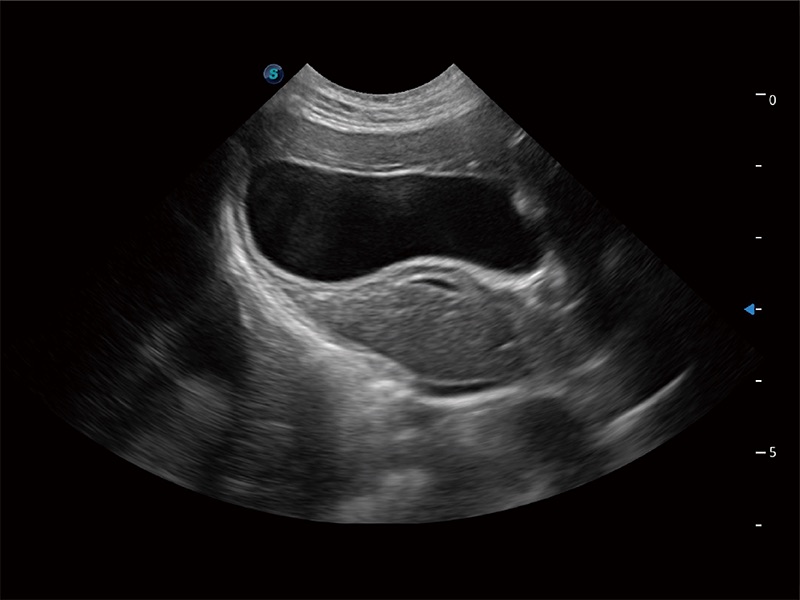

高性能和先進的臨床應用工具可以為動物醫(yī)生提供臨床信心。ProPet 80 搭載了先進的腹部和淺表應用工具,幫助醫(yī)生在日常臨床實踐中發(fā)揮前所未有的作用。

極大提升超低速微細血流的檢出能力,同時更精準地濾除軟組織和超聲信號,為獸用醫(yī)生提供以往無法通過常規(guī)血流獲得的疾病診斷信息。

在傳統(tǒng)二維血流成像的基礎上,呈現(xiàn)血流的立體感,具有動感的生命力之美。即便是微小的血管也能輕松應對,提高了血流的視覺敏感性。

操作簡便,無需高頻度外力作用即可真實反映組織的形變,快速評估腫瘤良惡性。

非線性融合造影成像充分利用諧波和基波信號,為難以觀察的血流進行增強顯像??捎糜诰€陣、凸陣、微凸陣、相控陣探頭。